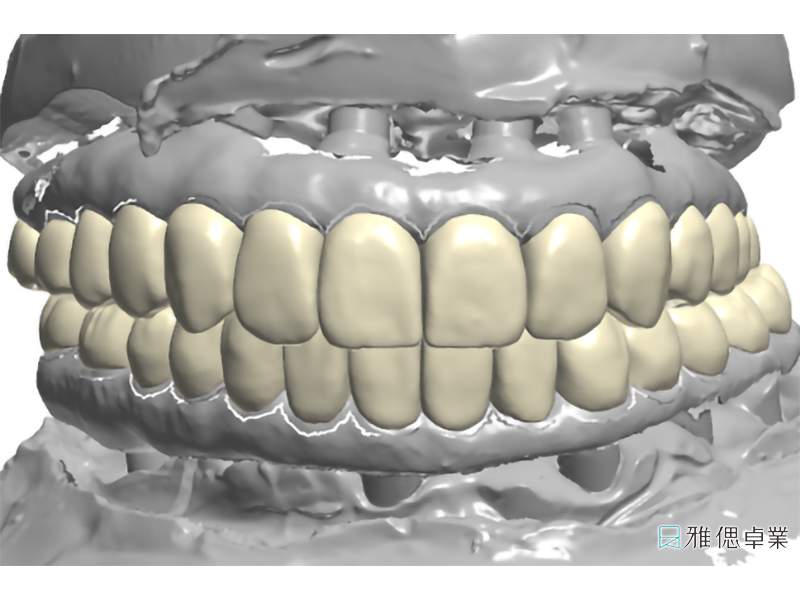

數位軟體設計假牙基座

全口假牙模型,模擬自然牙支台齒

假牙模型上顎

假牙模型下顎